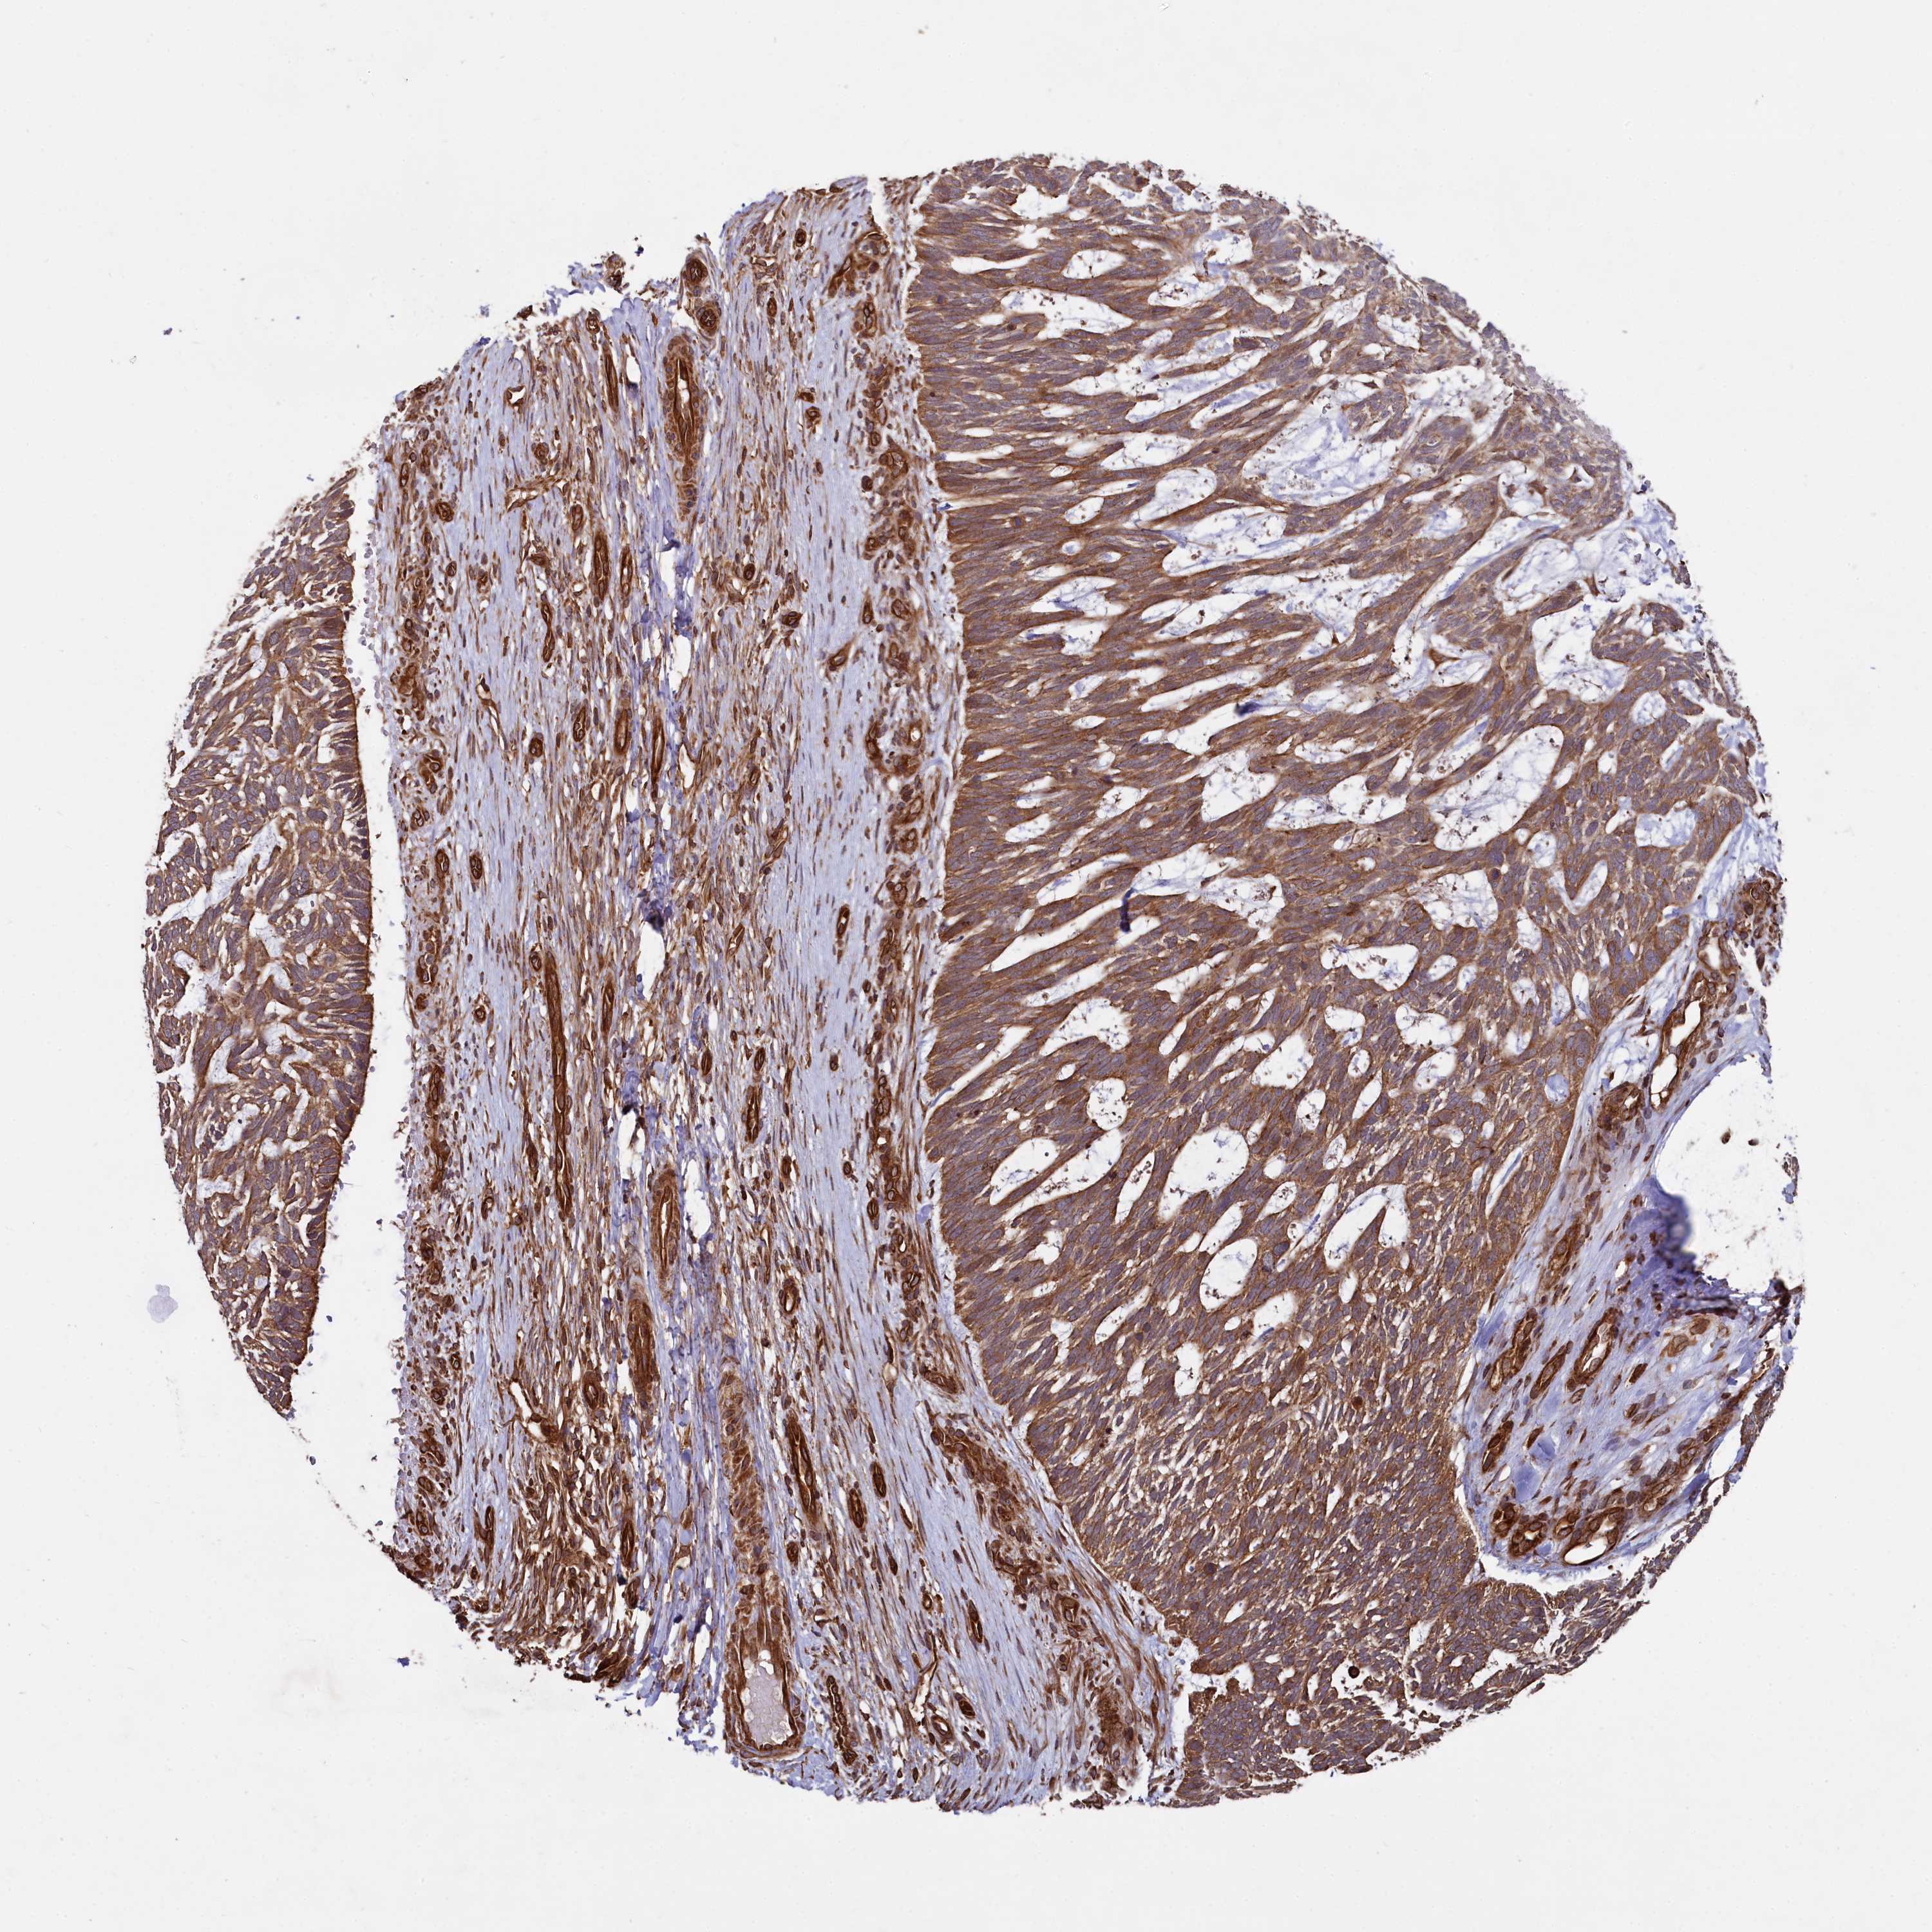

SKIN CANCER - Protein expressioni

A mouse-over function shows sample information and annotation data. Click on an image to view it in a full screen mode. Samples can be filtered based on level of antibody staining by selecting one or several of the following categories: high, medium, low and not detected. The assay and annotation is described here.

Antibody stainingi

Antibody staining in the annotated cell types in the current human tissue is reported as not detected, low, medium, or high, based on conventional immunohistochemistry profiling in selected tissues. This score is based on the combination of the staining intensity and fraction of stained cells.

Each image is clickable and will lead to virtual microscopy that enables deeper exploration of all samples and also displays staining intensity scores, fraction scores and subcellular localization as well as patient and tissue information for each sample.

Antibody HPA039807

Staining

High

Intensity

Strong

Quantity

>75%

Location

Nuclear

Cytoplasmic/membranous

Basal cell carcinoma

Squamous cell carcinoma, NOS

Squamous cell carcinoma, metastatic, NOS